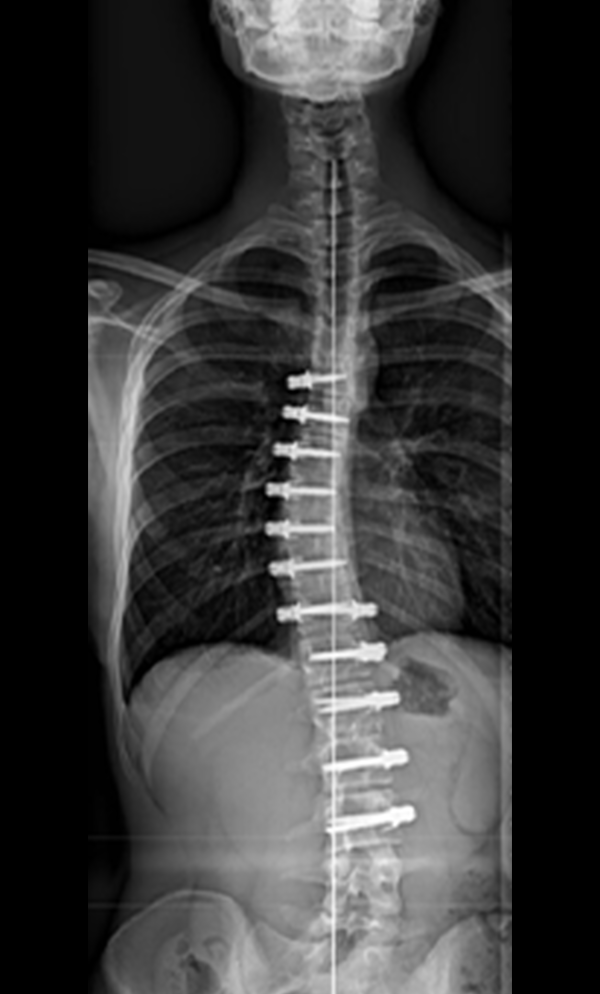

Vertebral Body Tethering (VBT) is a Minimally Invasive, Non-Fusion Technique used in selected Scoliosis cases to improve Spinal Alignment while maintaining more Natural Movement. It is commonly considered for progressive, flexible curves, often in the range of ~30–65° in appropriate candidates (exact criteria vary by surgeon and patient factors).

This procedure is performed through small side incisions, where the surgeon places anchors along the side of the curved vertebrae and connects them using a flexible tether cord. The tether is gently tensioned to correct the curve and support a more balanced spine, while remaining flexible to help preserve mobility.

Gallery : Before - After

After

Before